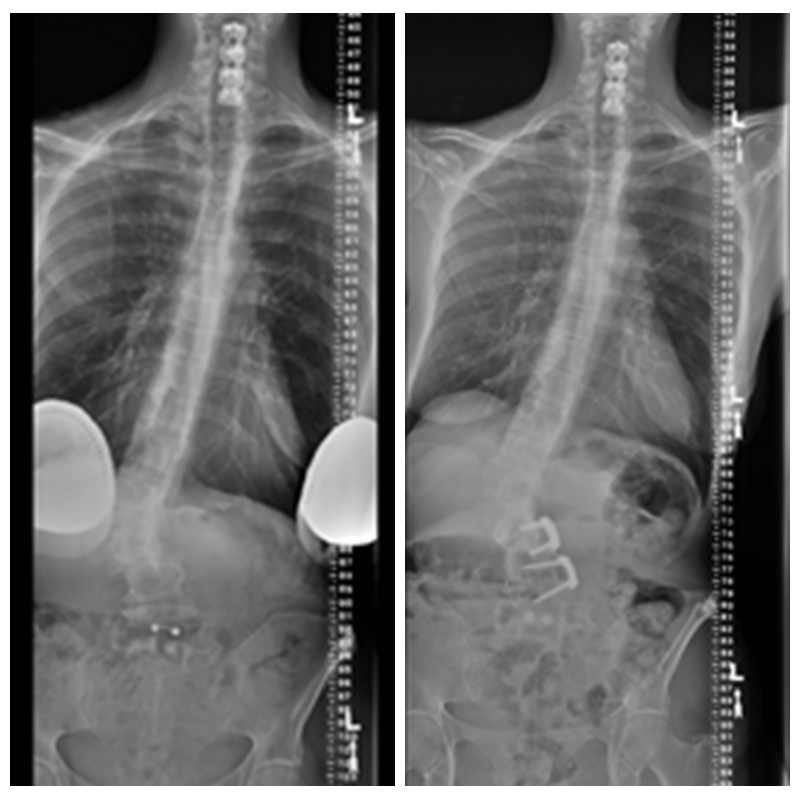

为患者行局部减压融合内固定术术后:

术后患者恢复良好,诉下肢疼痛症状完全消失,并且较术前能站的更直。

予患者行L3/4节段椎间孔减压,后路MIS固定。术后患者下肢疼痛症状完全消失。

行L4/5,L5/S1两个节段减压融合内固定术,术后患者下肢症状完全消失。

术后X线